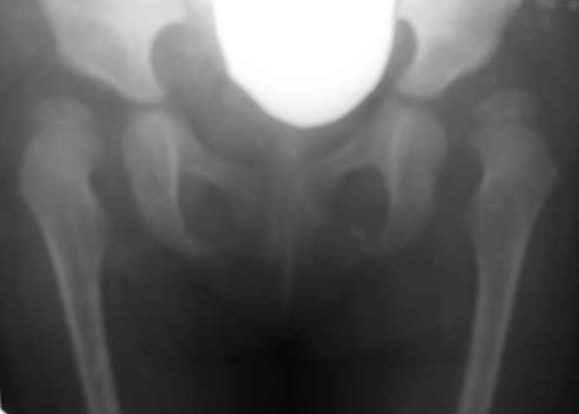

[Ortho] Дисплазия тазобедренного сустава у девочки 2х лет.

Здравствуйте, уважаемые коллеги. Хотел бы посоветоваться с Вами по

тактике лечения одного из наших пациентов. К нам обратилась девочка

2года и 4 мес. С анамнеза: в 10 месячном возрасте поставлен диагноз

врожденного вывиха бедер. Лечилась консервативно на данный момент.

Рг-картина неудовлетворительная. Посоветуйте, пожалуйста тактику

оперативного лечения.